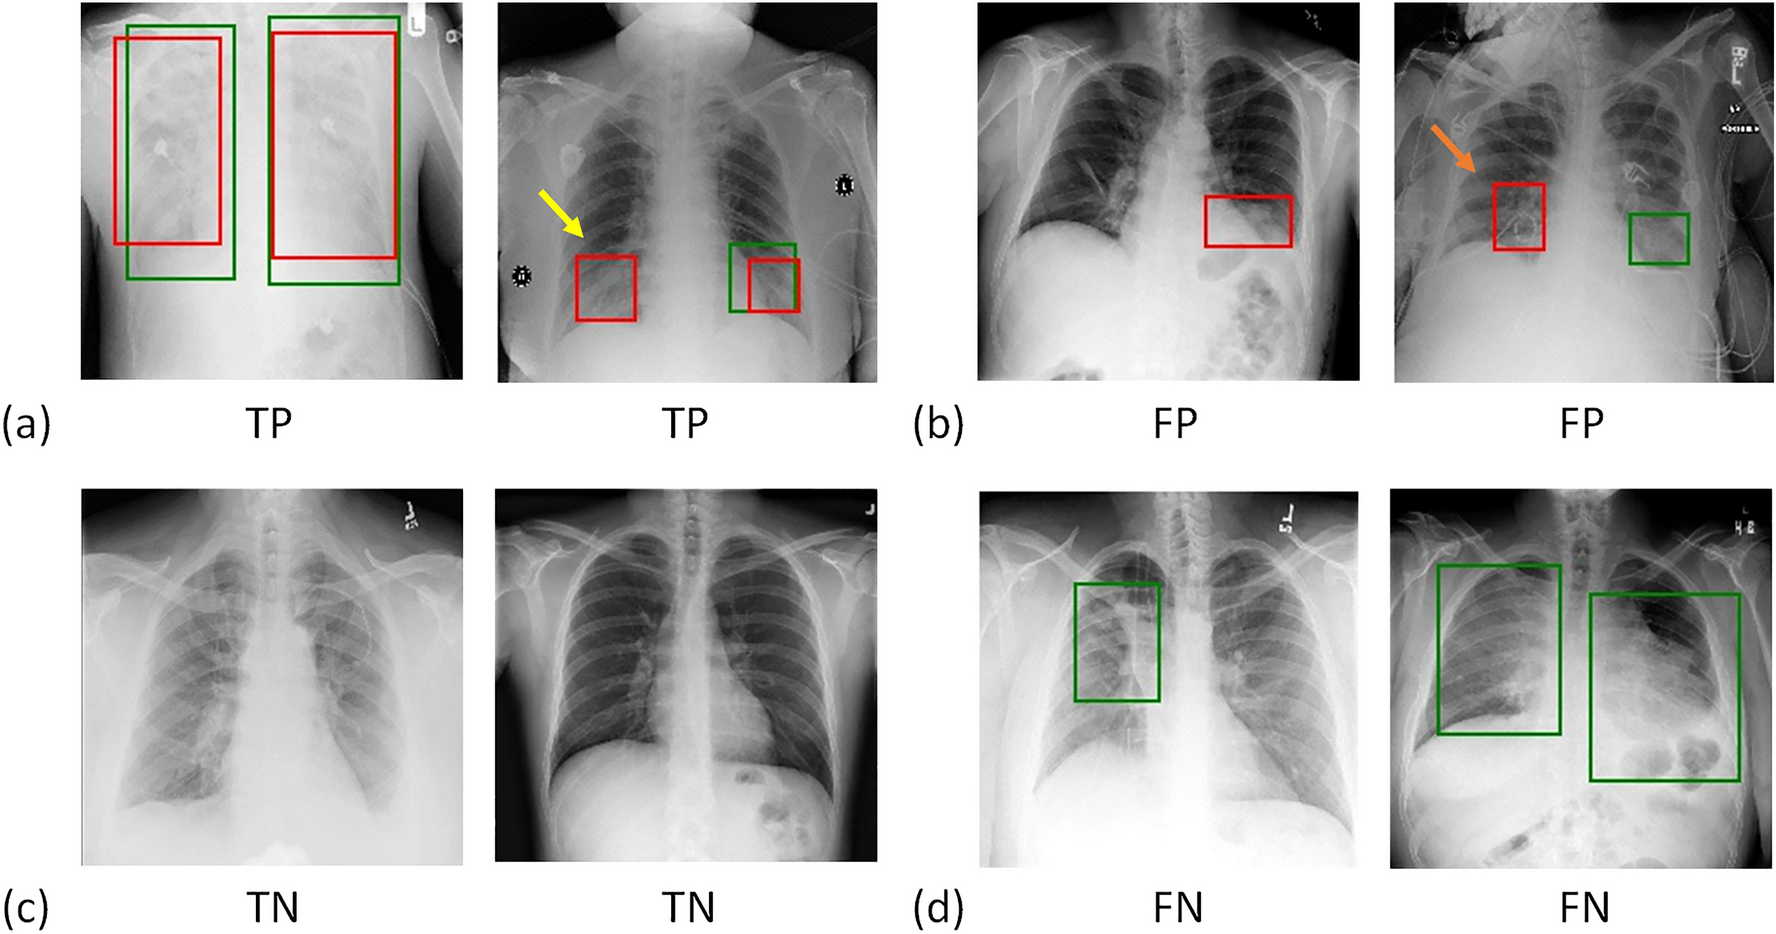

Figure 4

Example results of predicted cases, including (a) true positives (TP), (b) false positives (FP), (c) true negatives (TN), and (d) false negatives (FN). The true and predicted lung-opacity regions are denoted by green and red bounding boxes, respectively. Within the definitions of this study, we considered the second example in (a) to be a TP despite one of the two predicted boxes (yellow arrow) not overlapping with the reference box. We regarded the second example in (b) as an FP. Although the CXR model correctly predicted this as positive, the predicted region, indicated by the orange arrow, does not overlap with the green box.